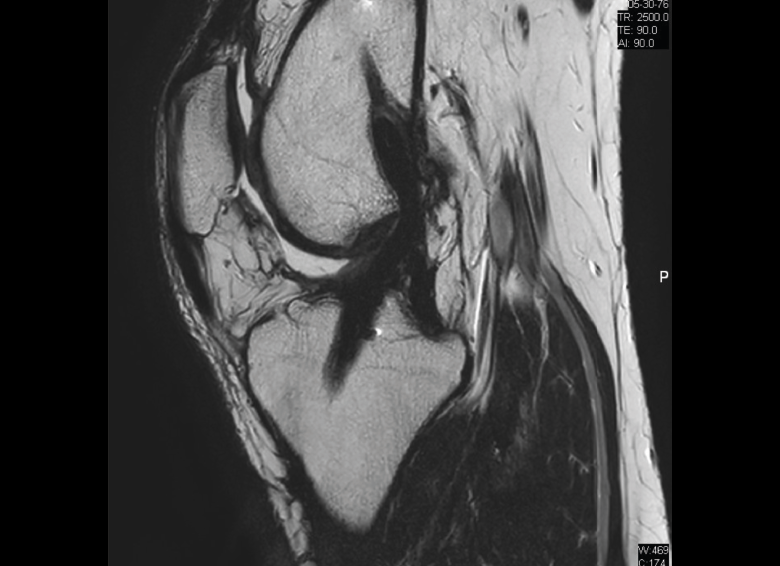

Figura 30. Corte de secuencia sagital T2 Fat-Sat de resonancia magnética de rodilla: menisco externo normal.

Figura 31. Corte de secuencia sagital T2 Fat-Sat de resonancia magnética de rodilla: menisco interno normal.

Figura 32. Corte de secuencia coronal T2 Fat-Sat de resonancia magnética de rodilla: rotura de menisco interno horizontal.

Figura 33. Corte de secuencia sagital T2 Fat-Sat de resonancia magnética de rodilla: menisco interno con cambios mucoides.

Figura 34. Corte de secuencia sagital T2 Fat-Sat de resonancia magnética de rodilla: rotura en asa de cubo desplazada al asta anterior del menisco externo.

Figura 35. Corte de secuencia coronal y sagital de resonancia magnética de rodilla: rotura en asa de cubo del menisco interno con fragmento desplazado al intercóndilo.

1.1. Meniscos

Se identifican como estructuras hipointensas en todas las secuencias, con asta anterior y posterior de morfología triangular.

La RM es la técnica de elección en el diagnóstico de la patología meniscal(17) (Figuras 30, 31, 32, 33, 34 y 35).